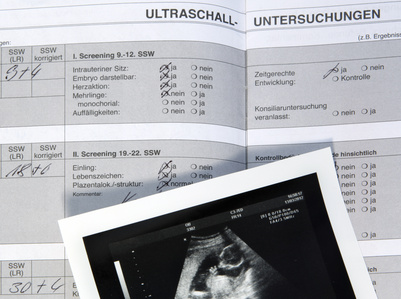

Zu den festen Bestandteilen jeder Vorsorgeeinheit gehören Routinekontrollen wie die Messung des Blutdrucks, Gewichtskontrollen sowie die Analyse der Urinwerte. Moderne Ultraschalluntersuchungen ermöglichen uns zudem, die Entwicklung Ihres Kindes genau mitzuverfolgen.

Nach Feststellung der Schwangerschaft und Erhalt der wichtigen Laborergebnisse stellen wir einen Mutterpass aus.

Der Mutterpass dokumentiert wichtige Untersuchungen und Ergebnisse, z.B. die Blutgruppe mit Rhesusfaktor sowie relevante Vorerkrankungen. Der Mutterpass gehört als ständiger Begleiter in der Schwangerschaft in die Handtasche.